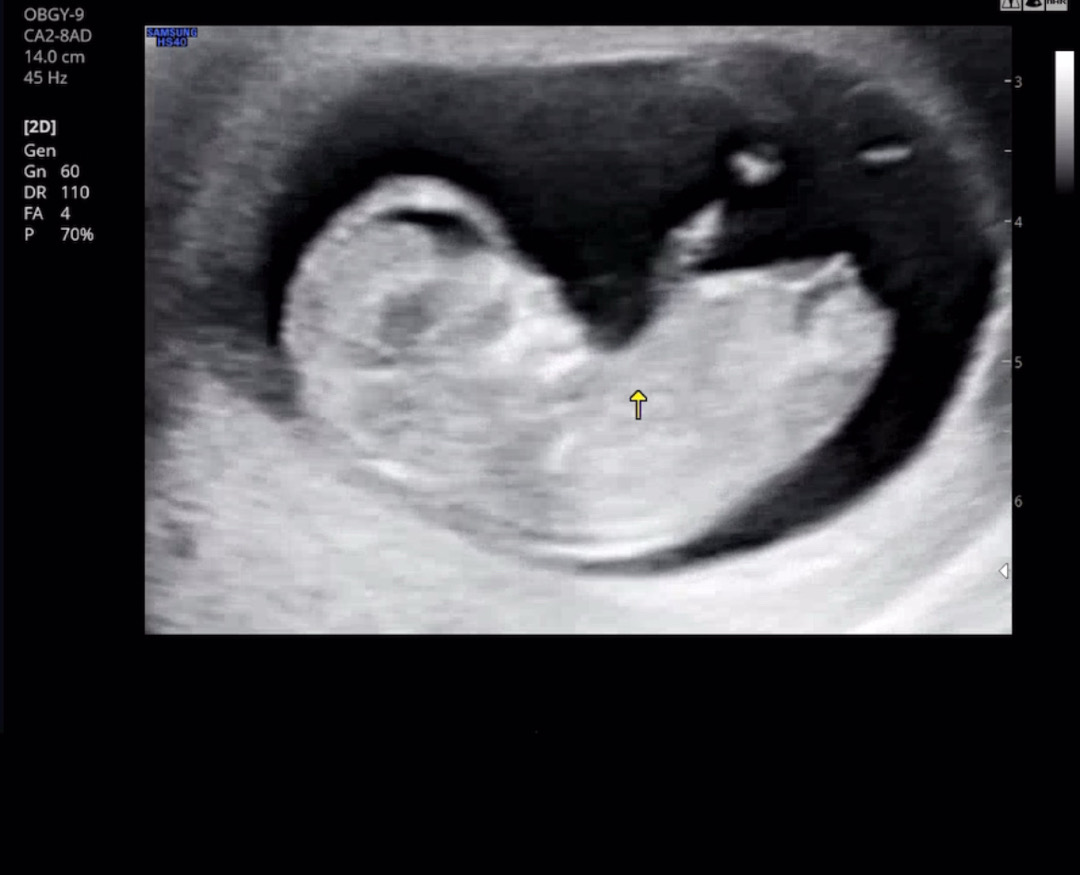

어떤 성별일까요 ^^

아직 11주차이지만 봐주세욤